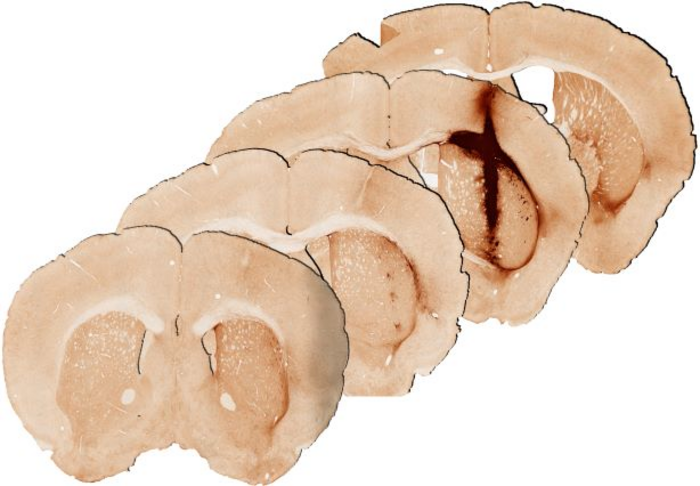

“We saw that the hydrogel incorporating myoglobin and stem cells repaired injured brain tissue. Analysis at 28 days after delivery of the hydrogel revealed significantly enhanced survival and growth of the new stem cells that are needed for healthy brain functioning, compared with a hydrogel without myoglobin,” Professor Parish said.

“We observed that the new tissue could be stimulated in a similar way to healthy brain tissue, providing the first evidence of the benefits of including oxygen delivery within a hydrogel to achieve the long-term survival and integration of stem cell transplants.”